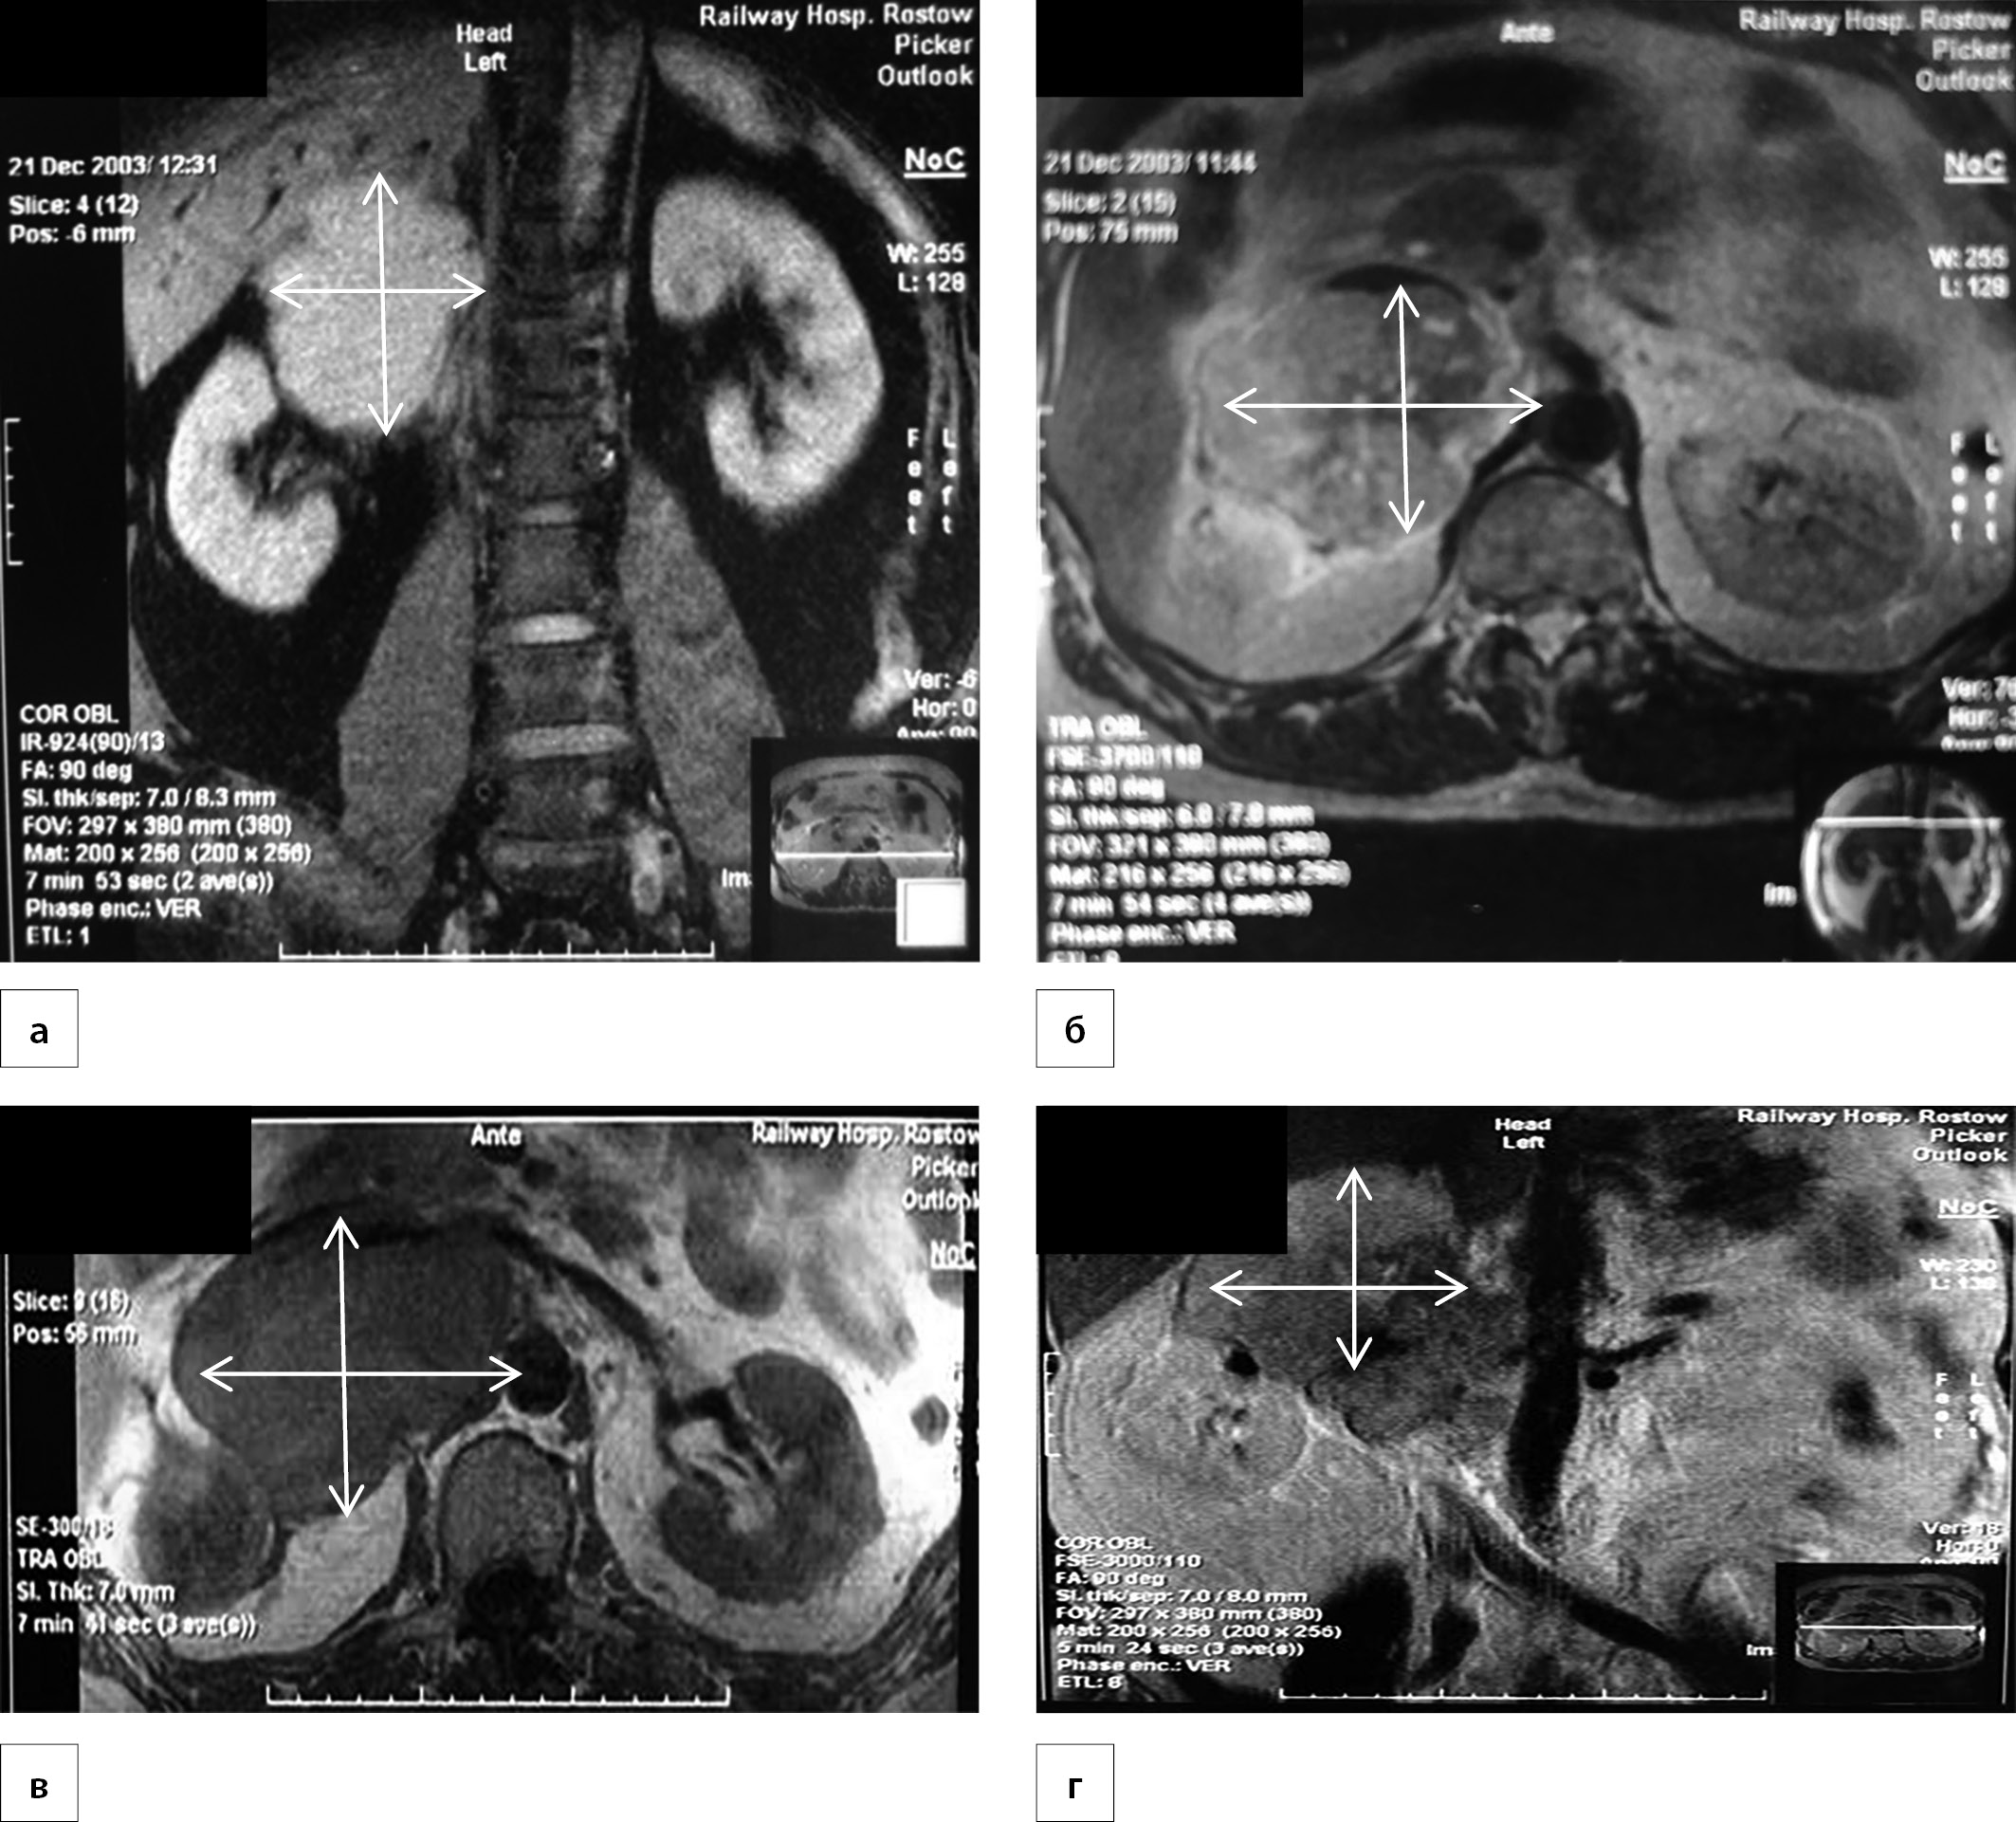

1. Рисунок 1. Магнитно-резонансные изображения лейомиосаркомы правого надпочечника, на снимках изображено четко очерченное неоднородное образование над правой почкой (указано стрелками): Т1-взвешенные изображения в коронарном срезе (а) и сагиттальном срезе (б, в, г). | |